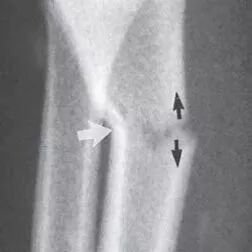

First, there is the fairly common greenstick fracture. This occurs when trauma to one side of the bone causes the other side of the bone to crack. The severity of a greenstick fracture can be very light – hard to see with the naked eye – or very severe, like the one in the image below.